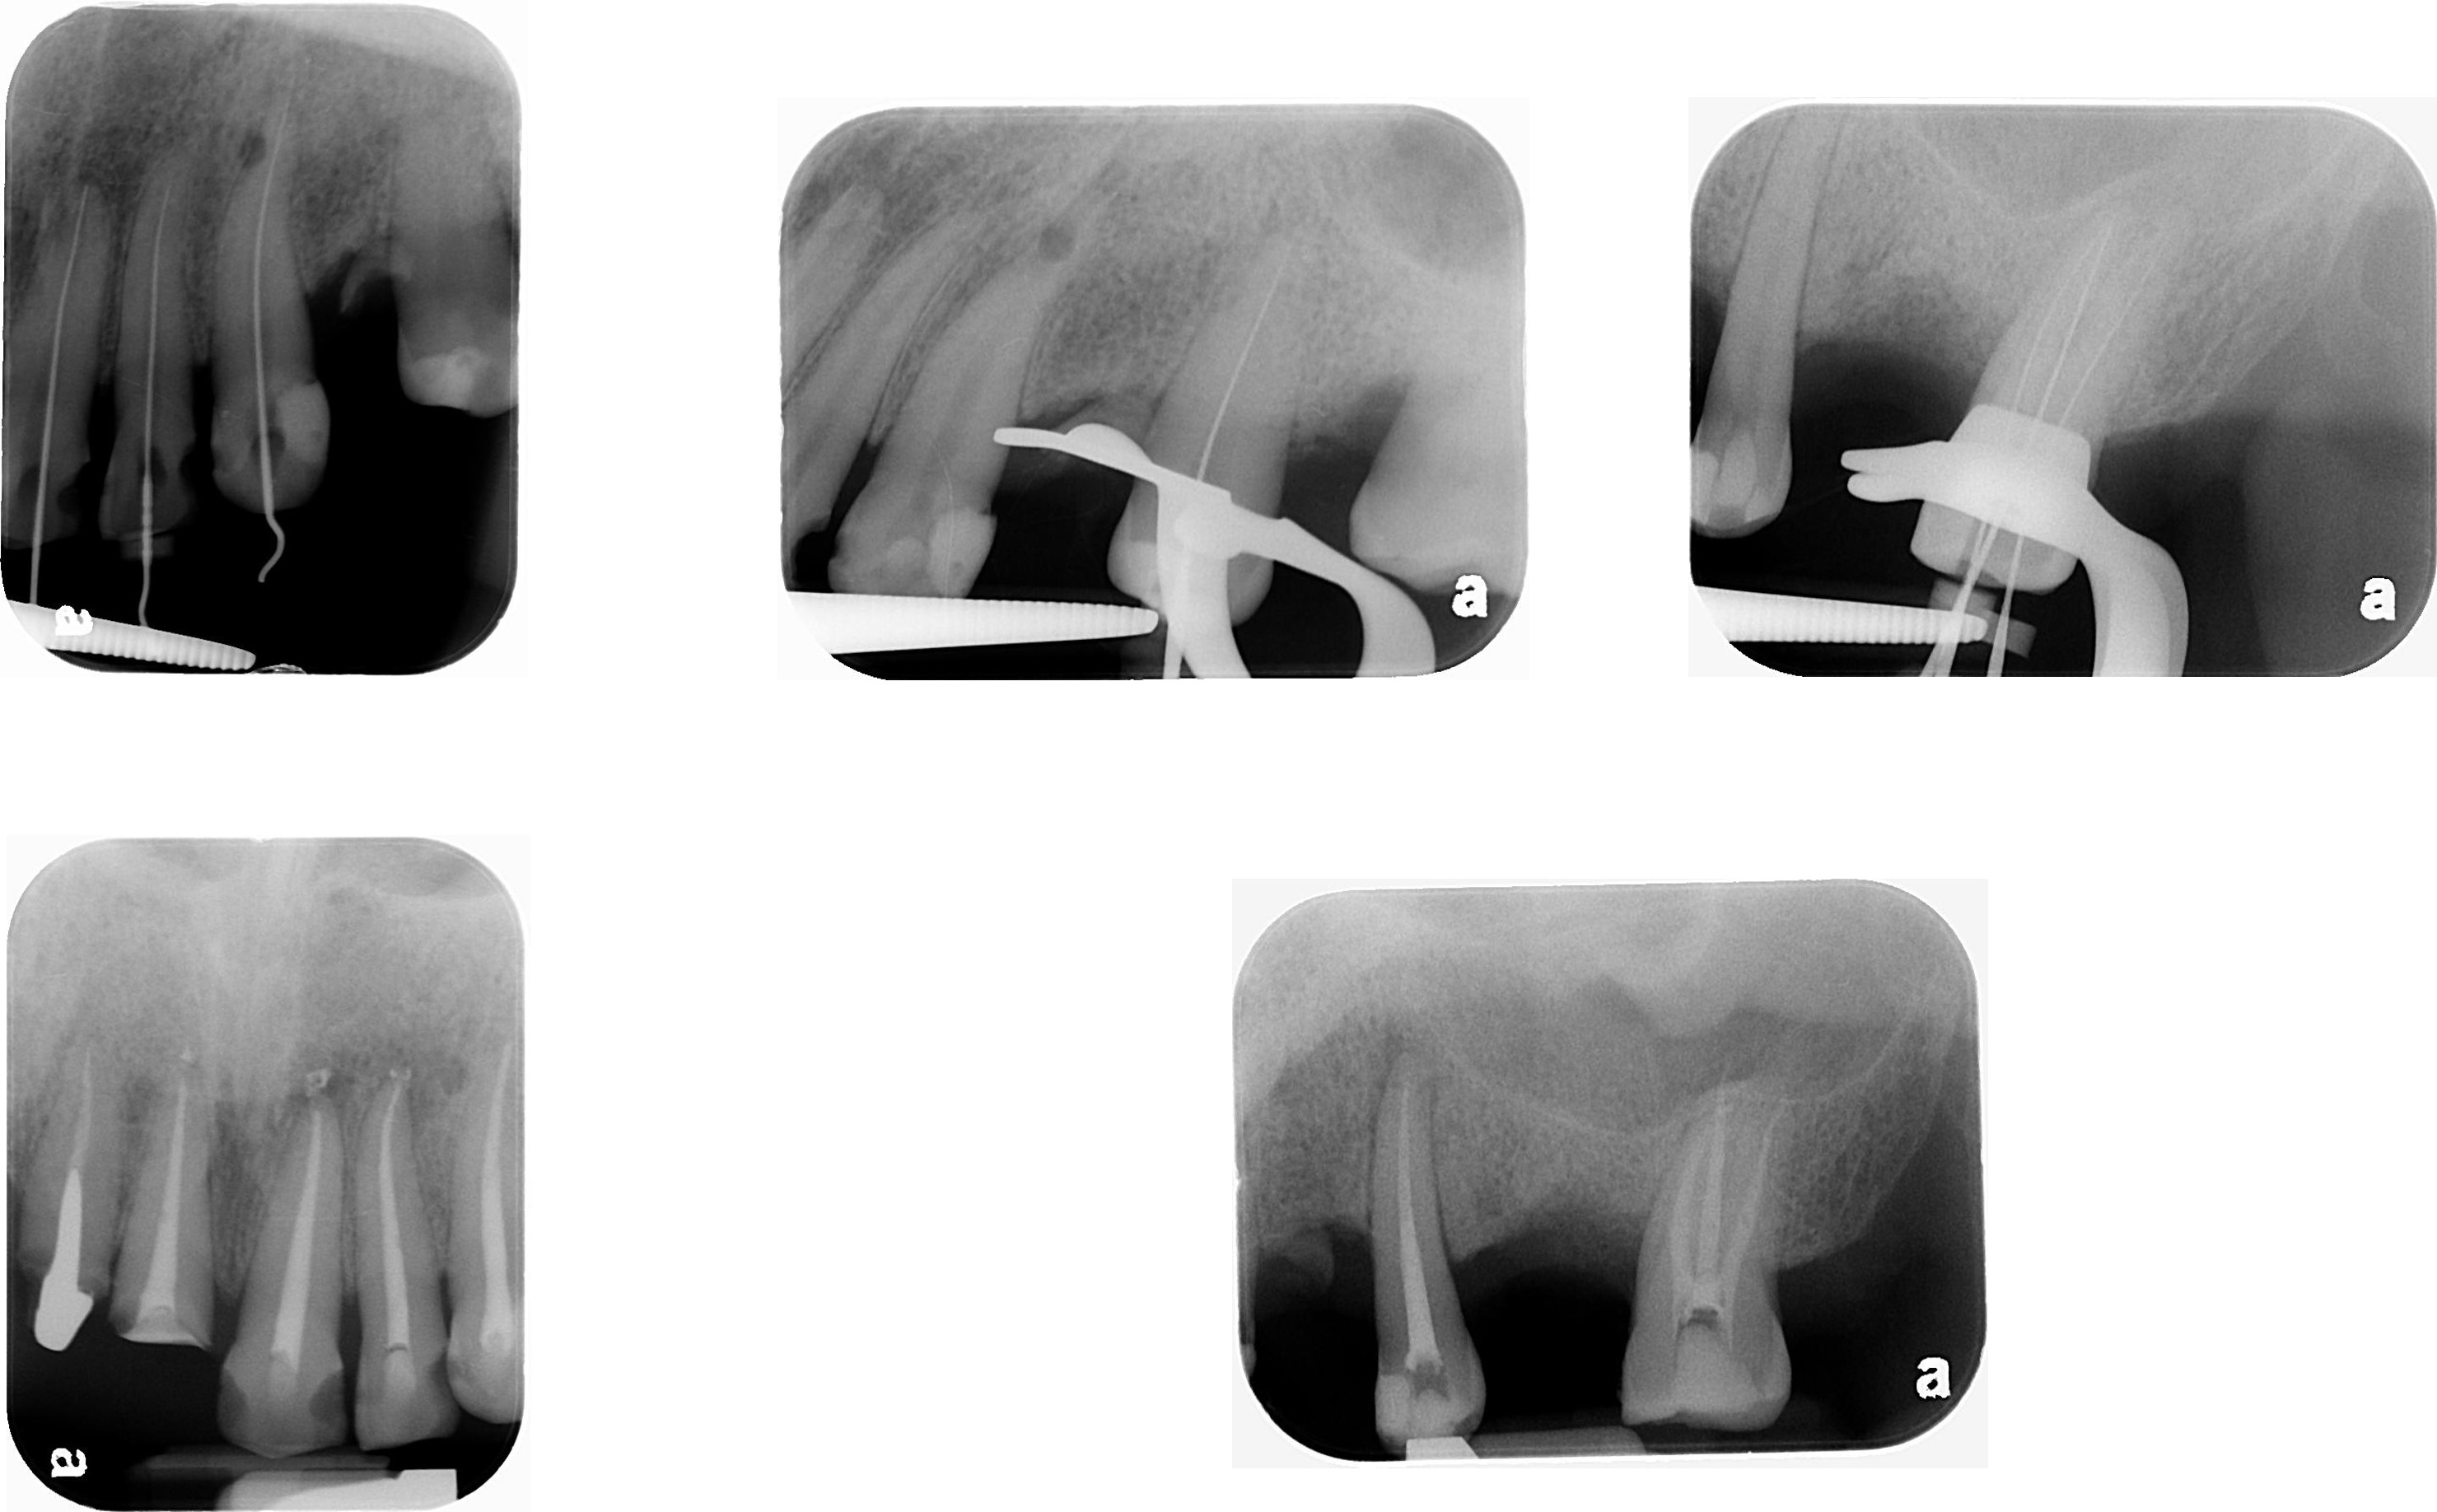

上顎牙齒根管治療

移除舊釘柱

上下顎二階手術

術後X光片

術前、術後比較